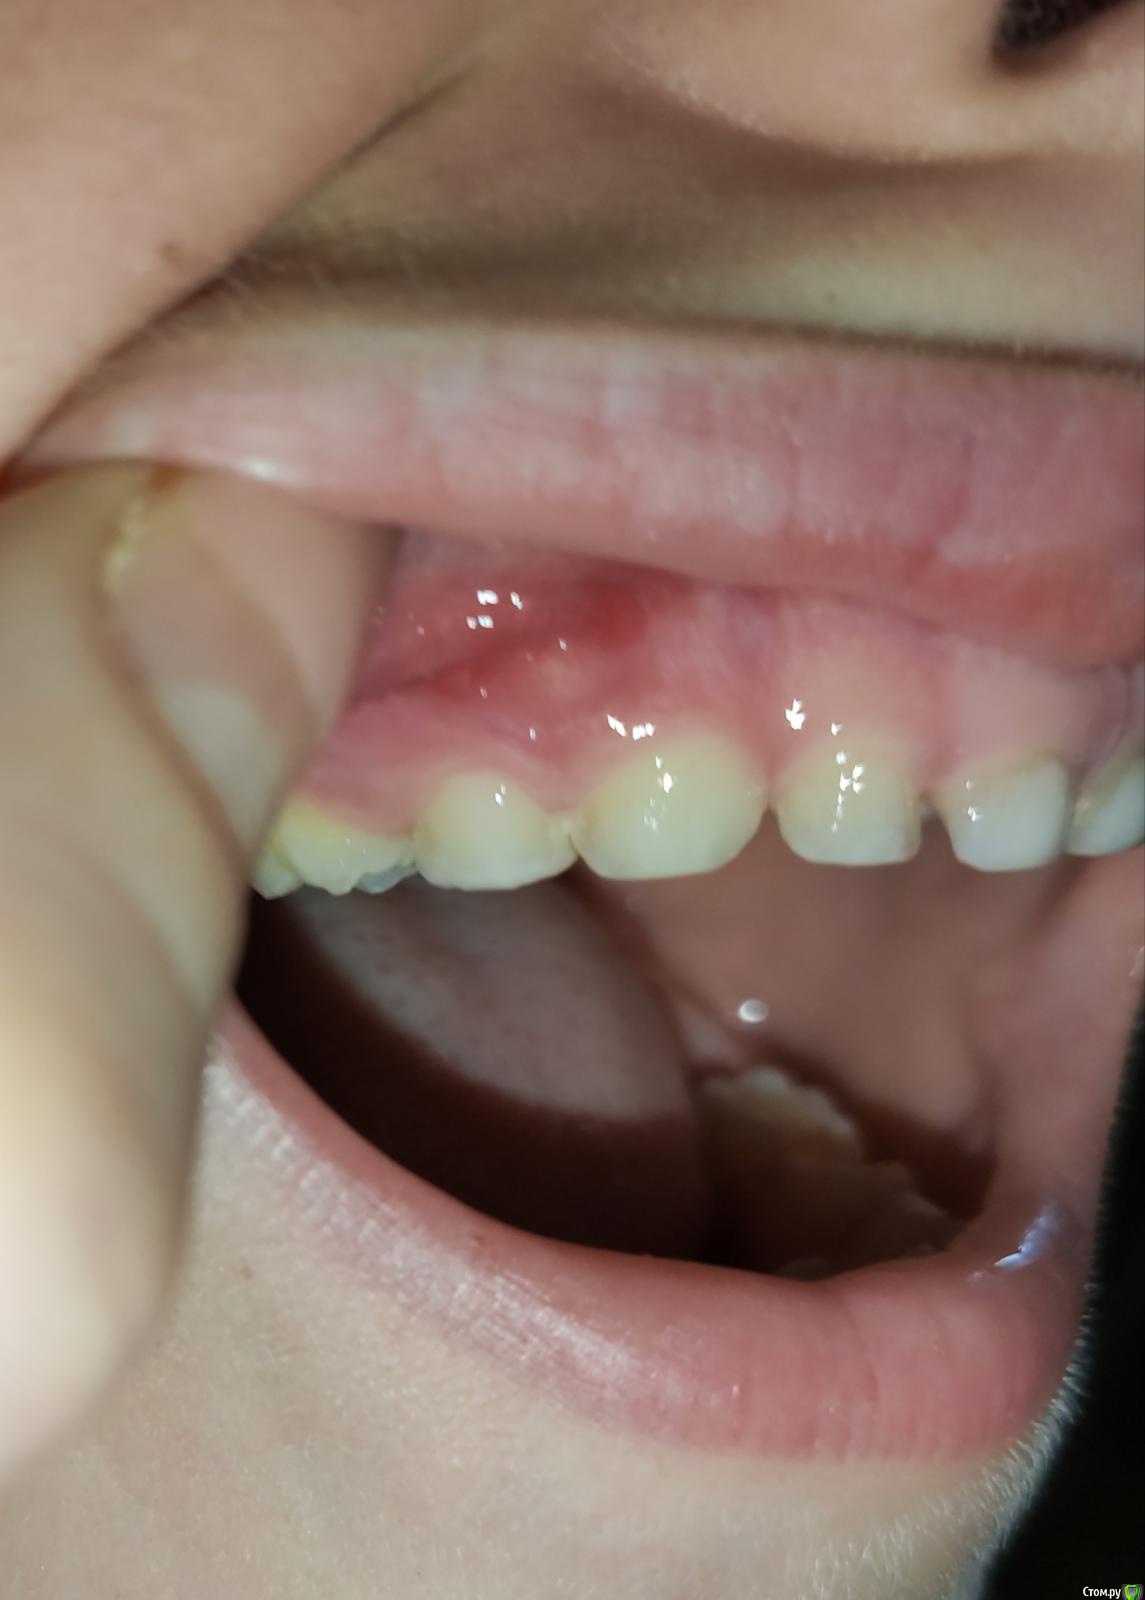

Ирина2511 Опубликовано 5 мая, 2020 Поделиться Опубликовано 5 мая, 2020 (изменено) Здравствуйте. Ребенку 6 лет и 9 месяцев. Начал жаловаться на боль в десне. При осмотре заметила покраснение и припухлость на десне и кариозную полость в зубе. Самочувствие в целом хорошее. Обратились к врачу, сделали снимок. Ответить флюс это или нет врач не смогла. Зуб живой, гноя нет. Поэтому решено было попробовать зуб спасти. Но врач сказала, что гарантии нету т.к корень начал рассасываться. Но добавила, что надо пытаться максимально сохранить все зубы, потому что смены верхних передних ещё не было. Прилагаю фото снимка и самой десны.Подскажите, есть ли смысл бороться за молочный зуб? Флюс это или не флюс? Изменено 5 мая, 2020 пользователем Ирина2511 Ссылка на комментарий